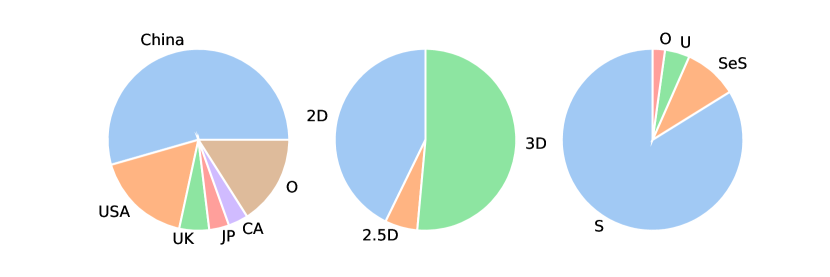

The database search retrieved 2,851 results. After title and abstract screening, the full texts of 206 reported studies were analyzed, but only 140 were found eligible for inclusion. Twenty studies using imaging acquisition other than CT (magnetic resonance imaging (MRI), positron emission tomography (PET), and ultrasound) were excluded. The list of excluded articles and the reasons for exclusion are reported in Section 2.5. Ten additional studies were retrieved after a manual check of the references. A total of 130 studies were included for full-text analysis (Fig. 2). By considering the involved countries (Fig. 3, left panel), China led the ranking with a share of 54.4%, followed by the United States (17.1%), the United Kingdom (5.3%), Canada (3.5%), and Japan (3.5%). In the majority of studies, 3D neural networks (Fig. 3, central panel) were used (51.4%), followed by 2D models (42.7%), and 2.5D (5.8%). By considering the learning type, the vast majority concern studies on supervised learning (83.8%), followed by semi-supervised learning (9.5%), and unsupervised learning (4.4%). Other types of learning (reinforcement, weakly, and continual) are reported in 2.2% of the studies (Fig. 3, right panel). Overall, there is a positive trend in the number of published articles in peer-reviewed journals, included in the present review, even though the data for the year 2023 are available until October 31st (Fig. 4). Notably, there has been a surge in the number of studies on DL for the segmentation of pancreas tumors in 2023. The 130 reviewed studies were published in high-quality peer-reviewed journals with a mean 2023 impact factor of 5.39 (latest available data according to the Web of Science). As can be seen from Fig. 5 the studies were most frequently published in prominent journals in the medical imaging domain, like Medical Imaging Analysis and IEEE Transactions on Medical Imaging, with 11 and 12 publications, respectively. Of note, there are other studies published in leading journals like IEEE Transactions on Pattern Analysis and Machine Intelligence, IEEE Transactions on Image Processing, and Nature Methods.